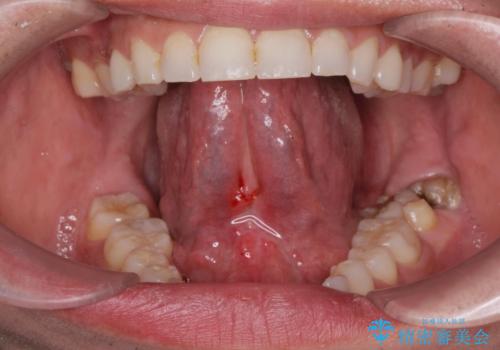

[ 舌小帯の形成術 ] ラ行の発音を改善したい

担当医 大元洋佑